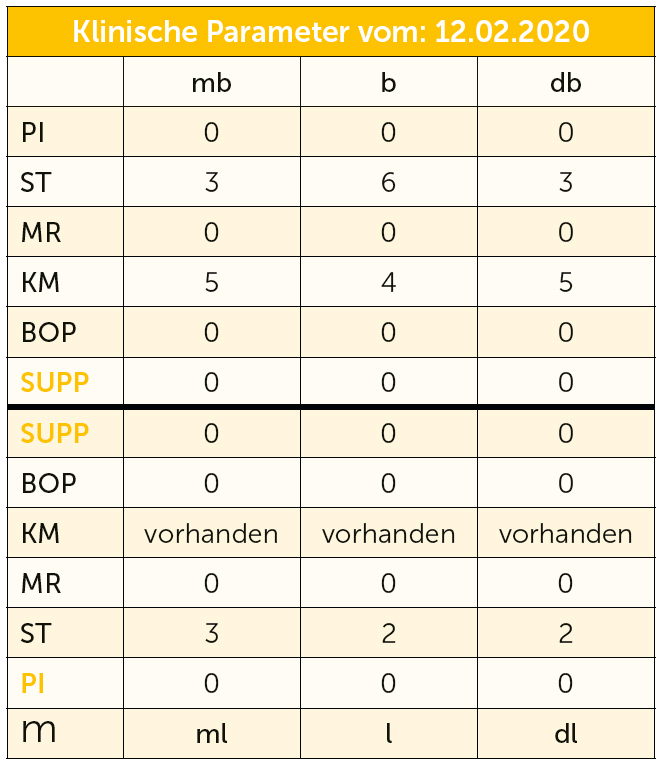

Abb. 3a bis h Falldokumentation mit Zustand nach Implantation und lateraler Augmentation alio loco: a) klinische Ausgangssituation mit Fistelung vestibulär in der Region 12; b) klinische Parameter (PI=Plaque Index 1-3, ST=Sondierungstiefe, MR=Mukosarezession, KM=keratinisierte Mukosa, BOP=Bleeding on probing, SUPP=Suppuration); c) radiologische Ausgangssituation mit initialem periimplantären Knochenabbau; d) operativer Zugang; e) Defektdarstellung nach Entfernung des periimplantären Entzündungsgewebes; f) Defektaugmentation mit einem Gemisch aus Eigenknochen und xenogenem Knochenersatzmaterial; g) Kollagenmembran; h) das aus dem Gaumenbereich entnommene Bindegewebstransplantat (BGT).

Abb. 3i bis m Falldokumentation mit Zustand nach Implantation und lateraler Augmentation alio loco: i) okklusale Ansicht mit eingebrachtem BGT vestibulär in der Region 12; j) Wundverschluss mit Naht; k) klinische Situation 9 Monate post operativ; l) okklusale Ansicht; m) klinische Parameter.